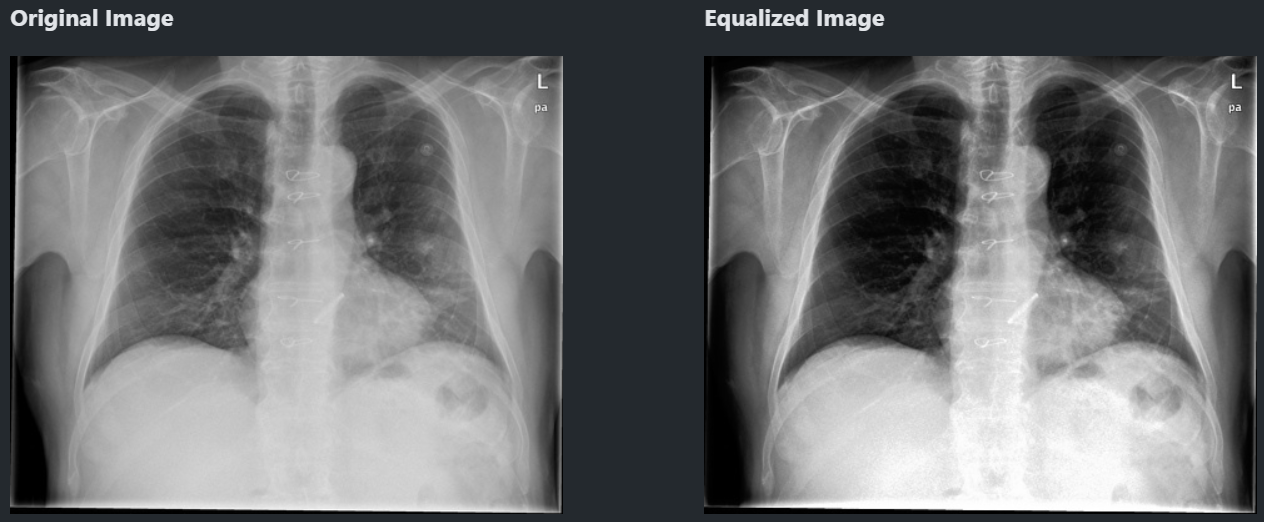

히스토그램 균일화

그냥 히스토그램 균일화

저 히스토그램을 서로 비슷비슷하게 맞춰주는 게 히스토그램 균일화. 기본적인 전처리임.

cv.equalizeHist(image)

- 명암이 좀 더 확실해지는데 대신 특징이 일부 사라질 수 있음.